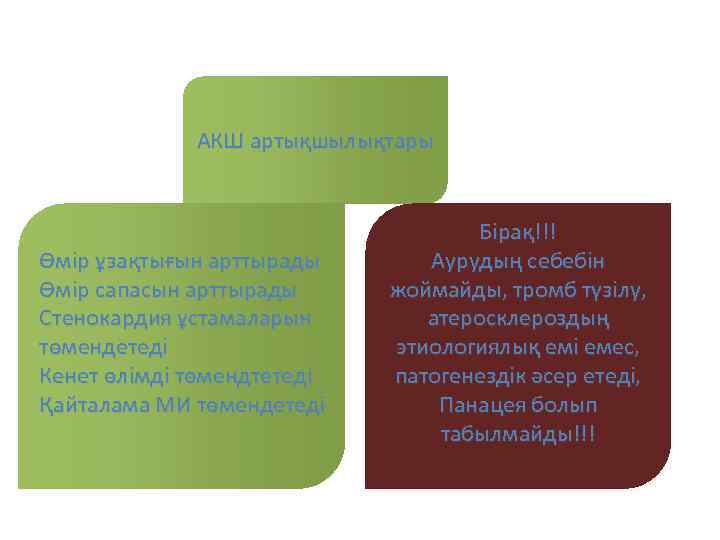

АКШ артықшылықтары Өмір ұзақтығын арттырады Өмір сапасын арттырады Стенокардия ұстамаларын төмендетеді Кенет өлімді төмендтетеді Қайталама МИ төмендетеді Бірақ!!! Аурудың себебін жоймайды, тромб түзілу, атеросклероздың этиологиялық емі емес, патогенездік әсер етеді, Панацея болып табылмайды!!!

АКШ артықшылықтары Өмір ұзақтығын арттырады Өмір сапасын арттырады Стенокардия ұстамаларын төмендетеді Кенет өлімді төмендтетеді Қайталама МИ төмендетеді Бірақ!!! Аурудың себебін жоймайды, тромб түзілу, атеросклероздың этиологиялық емі емес, патогенездік әсер етеді, Панацея болып табылмайды!!!